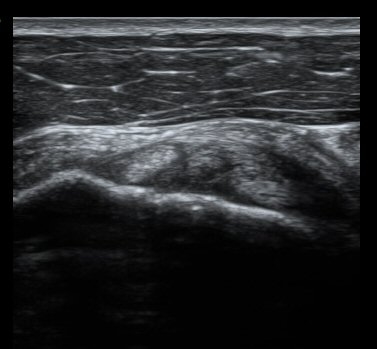

À̵ιڱٰí¶û¿¡¼­ À̵ιڱÙÀÌ Á¤»óÀûÀ¸·Î °üÂûµÇ°í ƯÀÌ ¼Ò°ßÀ» º¸ÀÌÁö ¾ÊÀ½(±×¸² 2).